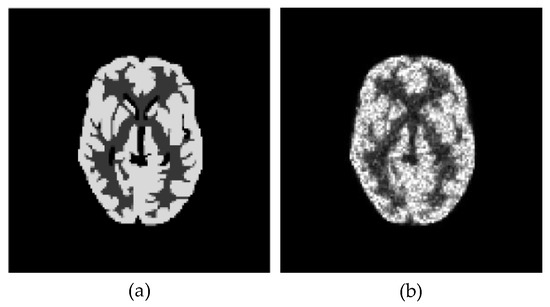

3.1. Numerical Studies Using Digital Phantom